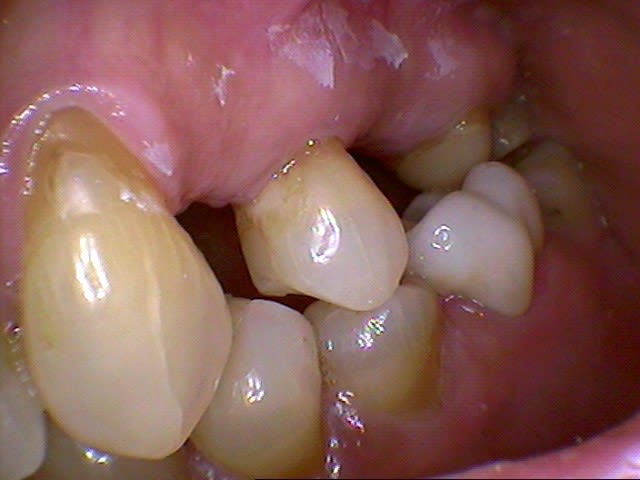

Je viens de recevoir mon cerec 4.02 et je n'ai que 2 jours de pratique, je vous livre mon avis en tant que nouvel utilisateur sans comparaison possible avec les versions antérieures:

Le logiciel me parait assez complet, bien structuré et interactif.

L'empreinte optique ne pose aucun problème après des gingivoplasties dans la même séance au CO².

la FAO est très rapide.

La précision est bluffante.

Mais une machine reste une machine...

Pour preuve, mes 2 premières couronnes ont du être refaites car,elles se sont docilement mise en contact avec leurs antagonistes en attente de prothèses en prenant des formes globuleuses, il fallait naturellement réaliser des retouches correctives sur le logiciel mais encore fallait-il le savoir!(leçon n°1)

J'ai réalisé plusieurs onlays dont 2 simultanés sans problème mais j'ai eu des difficultés à placer mon premier onlay dans une cavité où j'avais laissé volontairement des contre dépouilles devant être comblées par le composite de collage, il aurait mieux valu ne pas hésiter à tailler d'avantage (leçon n°2)

Les avantages sont indéniables et connus mais j'apprécie surtout le fait de pouvoir tailler sans soucis de casse lors de parois fines résiduelles puisqu'elles sont immédiatement consolidées par le collage des céramiques ainsi que de ne plus être limité par le volume des piliers de couronnes, ce qui change radicalement mes critères de taille.

Naturellement il me reste à suivre la courbe d'apprentissage et vos avis sont toujours les bienvenus.

Quelques illustrations: